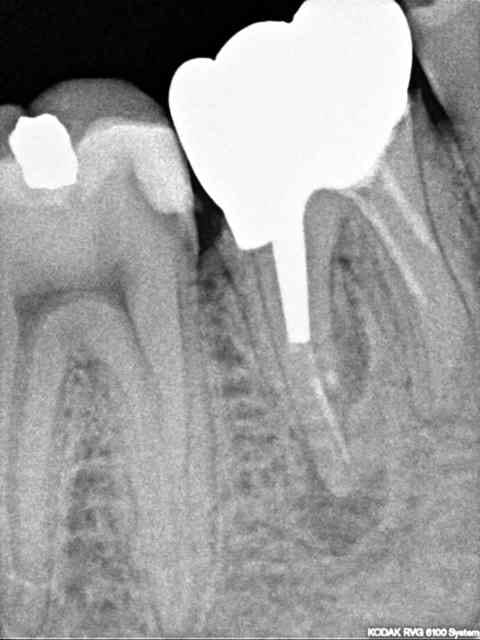

J'ai du mal à interpréter cette radio de 46 asymptomatique, RAS percussion et test de morsure.

Des avis ?

47 carie en mésial

46...plein de problème...

Donc dans une semaine : dépose couronne et tentative RTE. Mais je ne comprends pas l'image : on dirait qu'il y a deux images radioclaires distinctes associées à une image de résorption externe ou de fracture... Bon, je vais m'amuser.

Je pencherais pour une résorption, située dans la moitié de la racine distale, au niveau de l'apex du tenon, juste là où la racine est la plus concave.

Pour le retraitement ça semble compliqué ; la radio montre 2 racines en distal, il te faudra gérer la résorption (MTA) et retrouver la perméabilité canalaire pour éliminer l'infection.

S'il se confirme qi'il y a bien 2 racines, ou 2 canaux, j'en obturerais un entièrement au MTA (celui de la résorption) et l'autre à la gutta.

très forte chance de fracture racine mésiale à l'apex du pivot....exo cousin